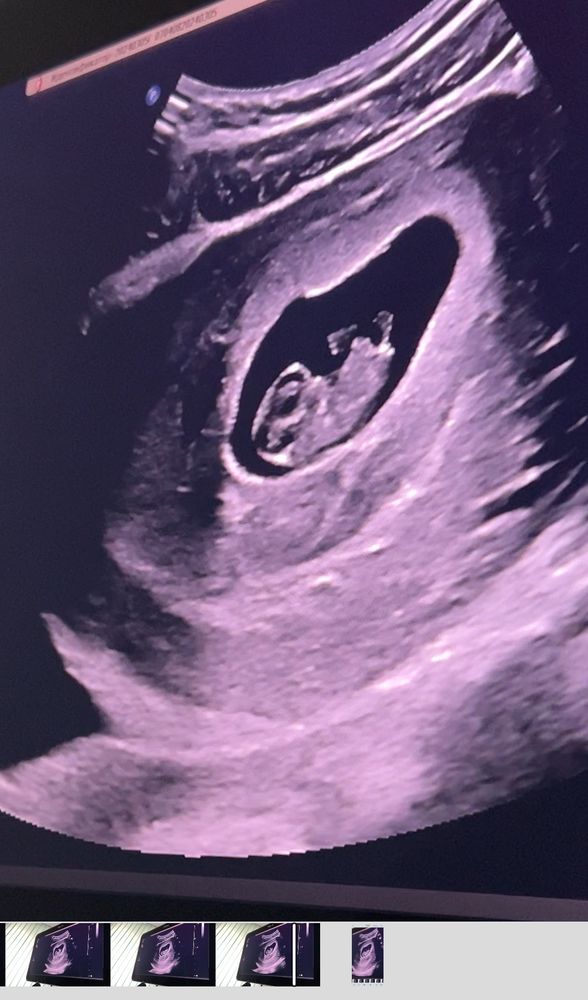

на утро, я побежала на узи, сердечко бьется, плод соответствует срокам, деформаций нету.

Через день с меня вышел большущий сгусток один и я снова пошла на узи. Обнаружили еще одну отслойку( скорее всего надорвалась,когда рвала от капельницы(один раз было)). Шейка матки закрыта,тонуса нету,сердечко бьется.

на фото нам 9 неделек🥰